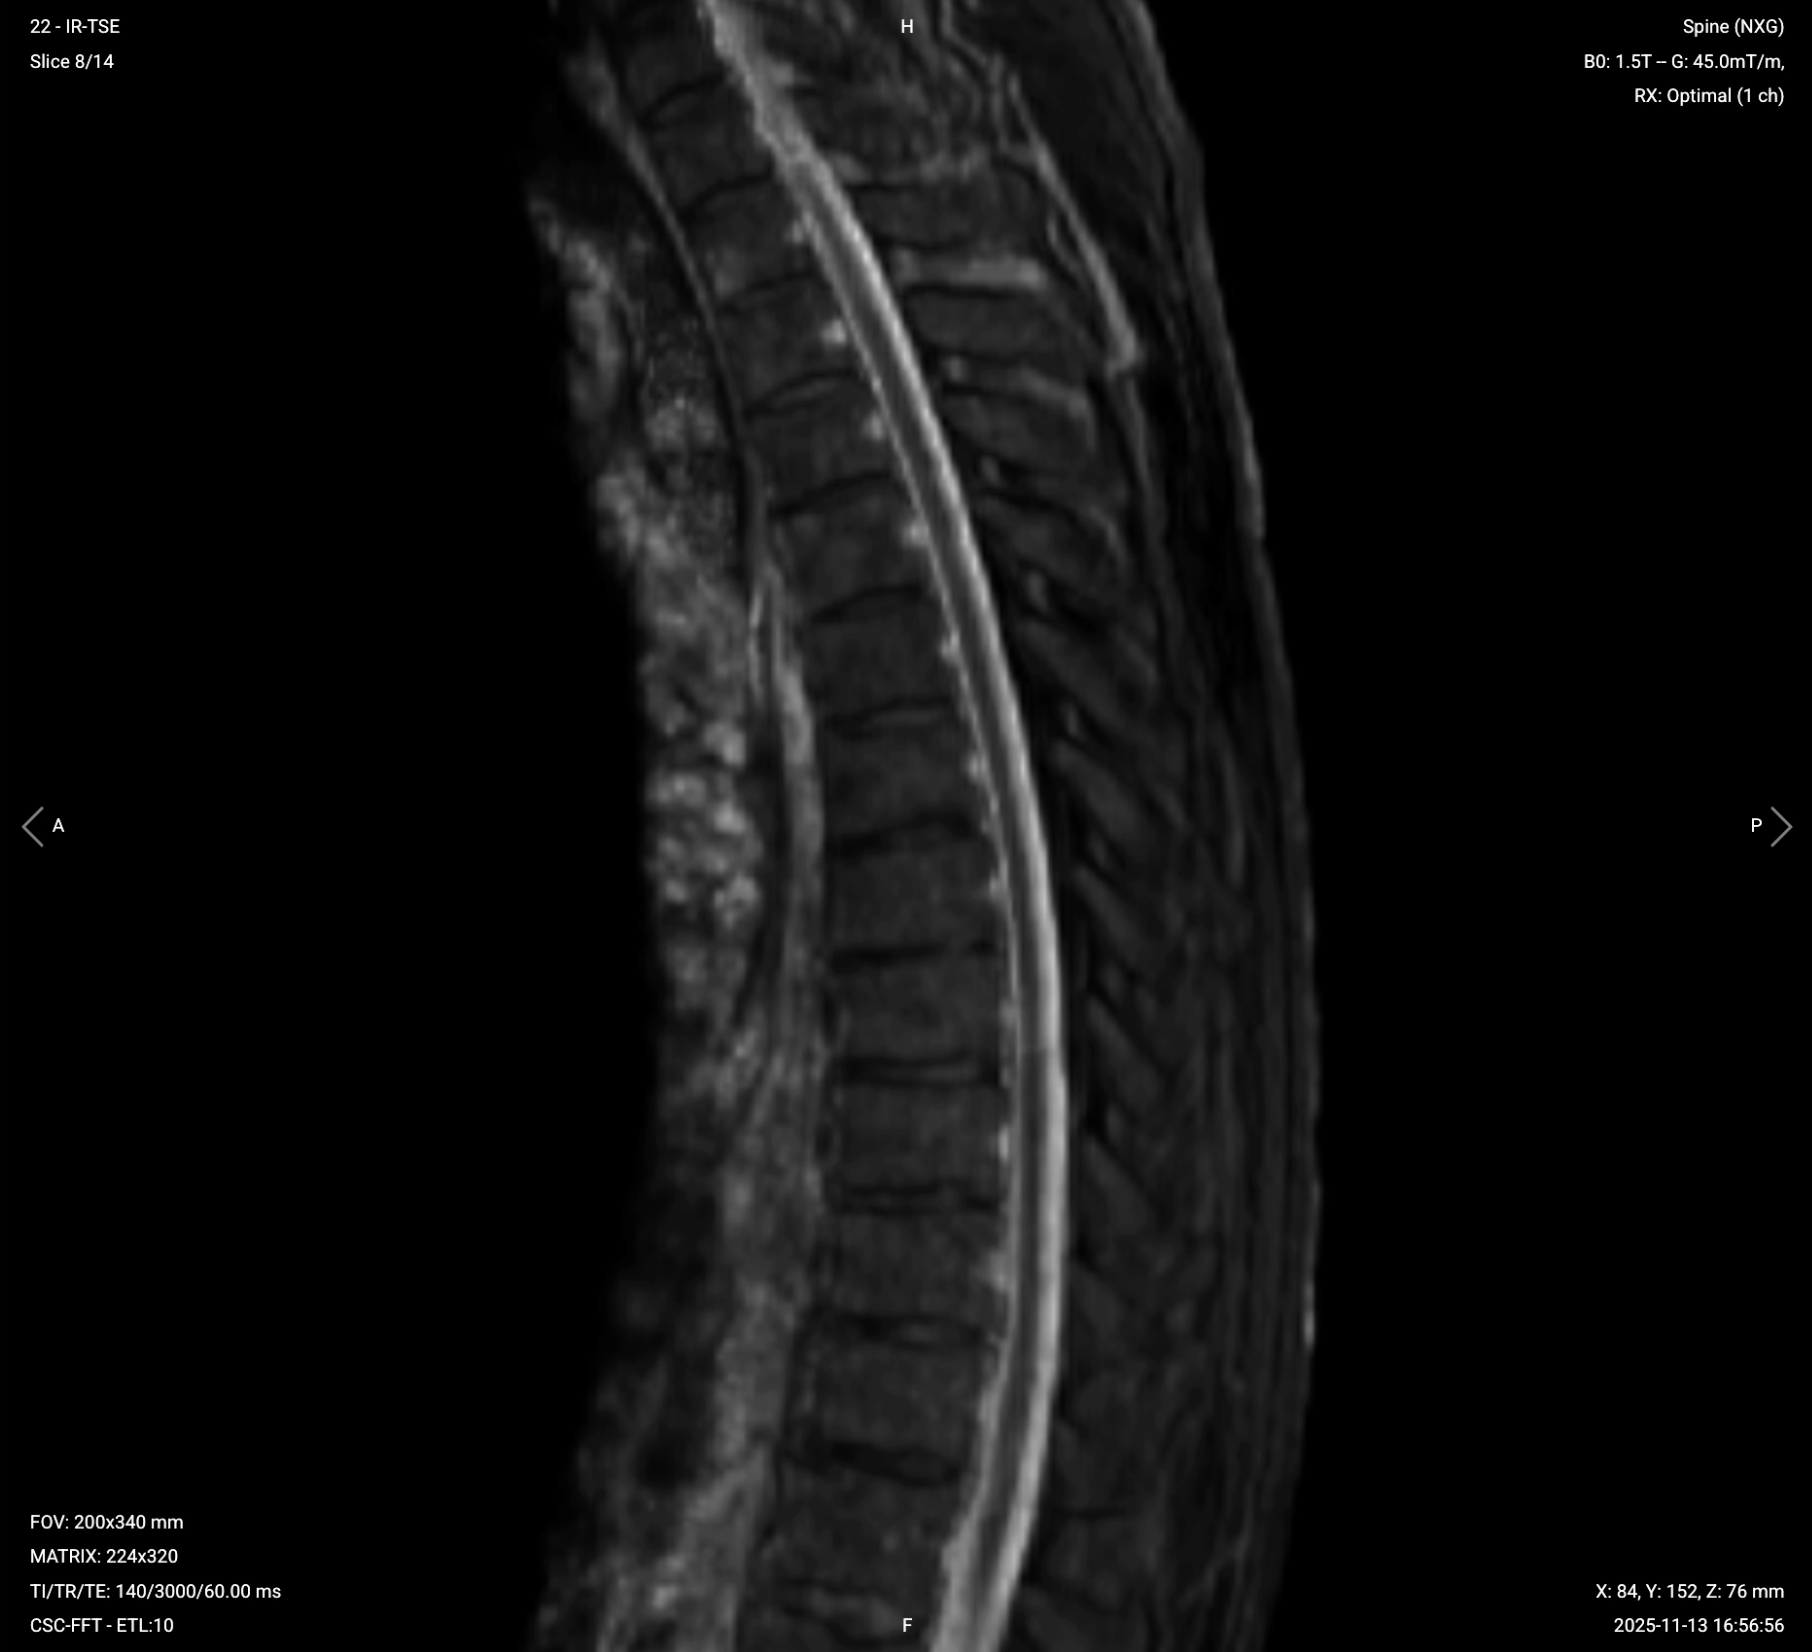

✅ Sagittal T2 TSE of Thoracic Spine – Correct Image Example:

Things to Look for in Sagittal T2:

STIR (Short Tau/TI Inversion Recovery) suppresses fat signals completely, which makes water-rich tissues stand out even clearer than with normal T2 TSE. This makes STIR ideal for detecting subtle fluid-related conditions like edema, inflammation, and infections, where increased water content would otherwise be obscured by fat.

In the thoracic spine, STIR is particularly useful for identifying bone marrow edema, infections like discitis or abscesses, inflammatory processes, and multiple sclerosis plaques. STIR provides high lesion visibility when water content might not be easily visible on standard T2 sequences.

We acquire STIR in the sagittal view to visualize the entire spine and detect any fluid-related changes across vertebrae or discs.

✅ Sagittal STIR TSE of Thoracic Spine – Correct Image Example:

Things to Look for in Sagittal STIR: